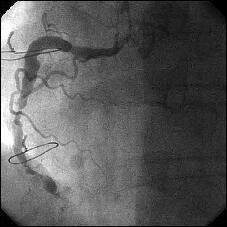

�Ǘ��72�Ώ����Brisk factor��HT, HL, DM�ł��B

��2�T�ԑO�̔��ǂƎv����Recent MI�ł��BLAD#7: total��Tristar3.0�~18?�����

�܂����B

����LCx ostium: 75%�ł��B������PCI���悤�Ǝv���̂ł����A�ǂ̂悤��strategy

���l������ł��傤���H

���Ȃ݂ɓ��@�ł�DCA�g�p�o���҂͂��܂���B

DCA�ł���l��A��Ă���A�Ƃ����I�������܂߂Č䏕��������K���ł��B

�ꉞ�A���ʂ�Y�t���܂��B